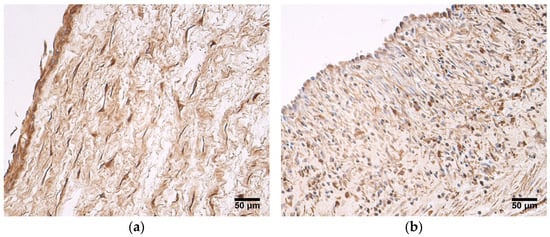

The inflammatory infiltrate in Wharton’s jelly and in the walls of the blood vessels was observed in two patient samples from the very preterm and moderate preterm birth umbilical cord group (Figure 1a), as well as in two patient samples from the late preterm birth and full-term birth umbilical cord group. In four samples, zones with multiple layers of amniotic epithelium cells could be visualized (Figure 1b). No other changes from the previously described well-known typical structures of umbilical cords were seen.

Figure 1.

(a) Inflammatory infiltrate seen in Wharton’s jelly and wall of an umbilical vein, gestational age—30 weeks; hematoxylin and eosin, X200. (b) Multiple layers of amniotic epithelium cells, gestational age—36 weeks; hematoxylin and eosin, X200.